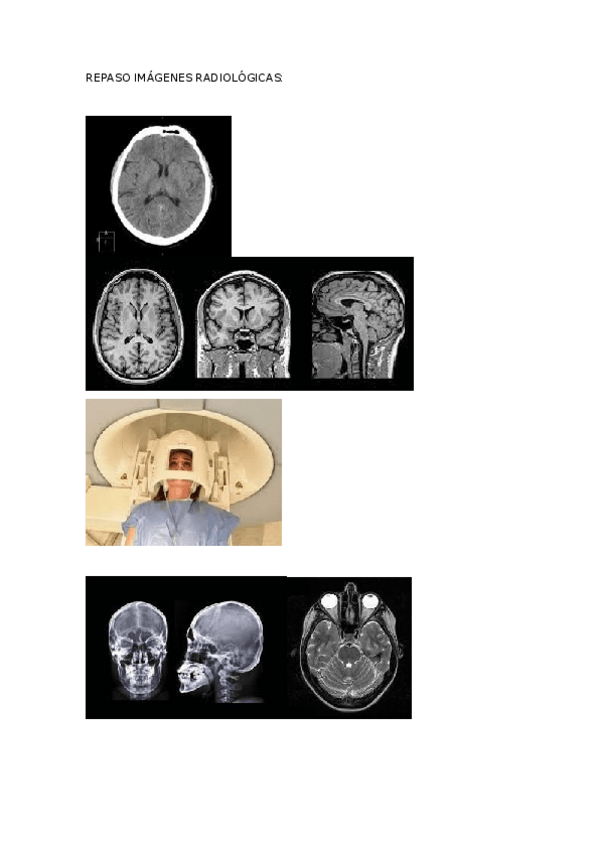

He publicado nuevos apuntes de Anatomía por la imagen: REPASO-IMAGENES-RADIOLOGICAS.docx

word